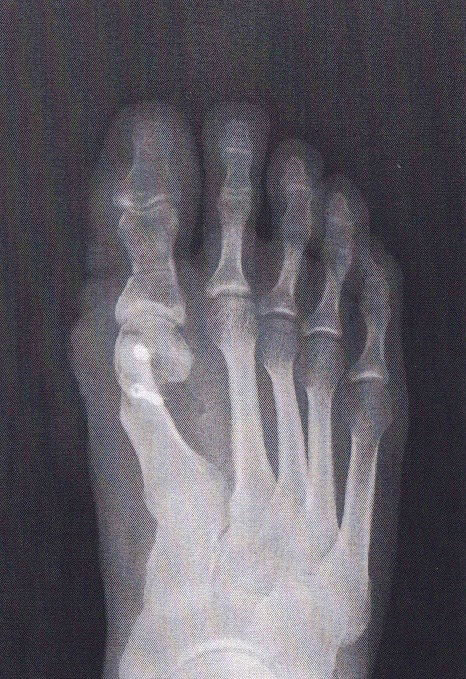

Alluce valgo

Guarda il casoalluce valgo

L’intervento consiste nell’eseguire delle osteotomia correttive (sia con tecnica tradizionale che mini invasiva) che permettono la correzione meccanica del primo raggio ripristinando un corretto allineamento.

Fig. 3 esempio radiografico di alluce valgo prima dell’intervento

Fig. 4 radiografia dopo correzione ottenuta con le osteotomie e la fissazione con 2 viti in titanio